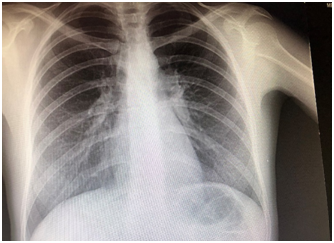

A 30 year old woman was admitted for dry cough, polyarthralgia, and subfebrile fever that developed following two weeks of amoxicillin-clavulanate treatment for maxillary sinusitis. Her past medical history was remarkable. The family history did not reveal any disease of medical interest. Four weeks before admission the patient developed fever (38.4°C), postnasal purulent discharge, and maxillary pain. WBC was 13.2×103/ml with 79 percent neutrophils, CRP: 55.5, ERS: 48mm/h. The patient was commenced on amoxicillin clavulanate 1000mg bid for fourteen days. Dry cough, dyspnea on exertion, polyarthralgia, and fever occured three weeks after amoxicillin clavulanate treatment. Chest x-ray was normal (Figure 1). Blood biochemistry was within normal limits. There was no radiologic abnormalitiy on joint films. Arterial blood gases; pH: 7.39, pO2: 84.2, and pCO2: 38.6mm Hg. ECG revealed sinus rhytm (84/min). Tuberculin test was negative. Chest CT showed bilateral multiple subpleural nodules in the lingula (one; 3mm), left lower lobe (multiple; 1-2mm), right lobe anterior segment (two; 5mm and 15X10mm) (Figure 2). Serum ACE was 24U/L. Sputum smear and culture were negative for bacteria, mycobacteria, and fungus.

Figure 2 Chest CT revealing pulmonary nodules.

It has long been known that many drugs, including antibiotics can induce DIL or vasculitis.1,3 Patients can be designated as DIL or vasculitis according to the accepted definitions, clinical, and serological findings. We present a case that presented with an atypical clinical picture of vasculitis following amoxicilline-clavunate treatment for maxillay sinusitis revealing overlapping manifestations of DIL and vasculitis5,6 due to amoxicillin-clavulanate. The final diagnosis was DIL due to positive anti-histone antibody. After steroid treatment, the patient showed an outstanding outcome with resolution of symptoms, clinical, laboratory, and radiologic findings. The patient was a diagnostic challenge for the clinician because the risk of developing DIL with amoxicillin-clavunate is extremely rare.4,6,7 Moreover, the distinction between DIL and vasculitis was not achievable due to the the significant overlap of the clinical manifestations between these two entities in our case. DIL patients present with various manifestations like arthralgia, pericarditis, pleuritis, and fever. Dry cough, subfebrile fever, and polyarthralgia were the predominant symptoms in our case. Chest CT revealed pulmonary nodules and enlarged mediastinal lymph nodes that are unusual in DIL. And thirdly, the clinical manifestations were atypical for DIL. Notably the presence of subpleural nodules and the enlarged mediastinal lymph nodes identified by chest CT lead to diagnostic confusion.